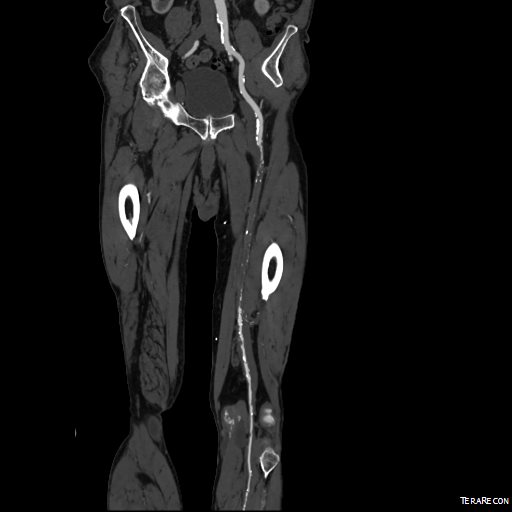

The patient is 70 year old woman with prior history of smoking who developed severe claudication and near rest pain. She was unable to walk more than 50 feet before having to stop due to severe leg pain. On exam, neither femoral artery pulses were palpable. PVR’s (pulse volume recordings) and ABI’s (ankle brachial index) are shown below.

PVR’s demonstrate the presence of severe inflow (aortoiliac occlusive disease or AIOD). CTA was acquired and the findings were consistent with the PVR’s.

There was diffuse bilateral iliac atherosclerotic plaque with occlusion of the right common femoral artery and left common and external iliac artery. The 3DVR (three dimensional virtual reality) reconstruction image below shows this as well as the abdominal and pelvic wall collaterals feeding the legs around the occluded iliofemoral system.

Plans were made to perform a hybrid common femoral and profunda femoral endarterectomy, remote external iliac artery endarterectomy (EndoRE), and common iliac artery stenting. The specific challenges to this case was getting into and staying in the true lumen. Typically, this is easiest to achieve from a left arm access with wires being pushed antegrade, but in a smaller person, particularly woman, this increases the chances for access site complications. My plan was to expose both common femoral arteries and get control of the external iliac arteries at the inguinal ligament and the profunda femoral arteries at the point the proximal plaque dissipated -typically at the second branch point, and then get micropuncture access of the right iliac system by accessing from the common femoral plaque. This would give me true lumen access, and with a sheath and curved catheter (VCF in this case, but a similarly shaped OMNI Flush catheter would do as well), wire access up and across the occluded left iliac system could be achieved and the wire retrieved from the left common femoral artery. This up and over access with the wire allows for control of the aortic bifurcation and both iliac systems.